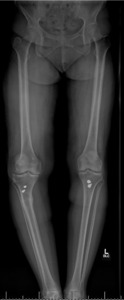

Pre-operative radiographs demonstrated Kellgren-Lawrence grade 4 tricompartmental osteoarthritis, 12° of tibial varus, a 22 mm deviation of the mechanical axis toward the medial side of the knee center, and an apex of angulation located 6 cm below the joint line (Figures 1 and 2). A follow-up computed tomography scan confirmed the absence of rotational malunion.

The total estimated blood loss was 300 mL, and no transfusion was required. The patient tolerated oral intake on the evening of surgery, completed her first physiotherapy session the following morning, and ambulated fifty feet with a rolling walker while wearing the hinged knee brace locked in extension. Following ambulation, full length lower extremity films were re-obtained, demonstrating neutral mechanical hip–knee–ankle axis (Figure 5). She was discharged home on post-operative day two with acceptable pain control and an incision that was clean, dry, and intact.